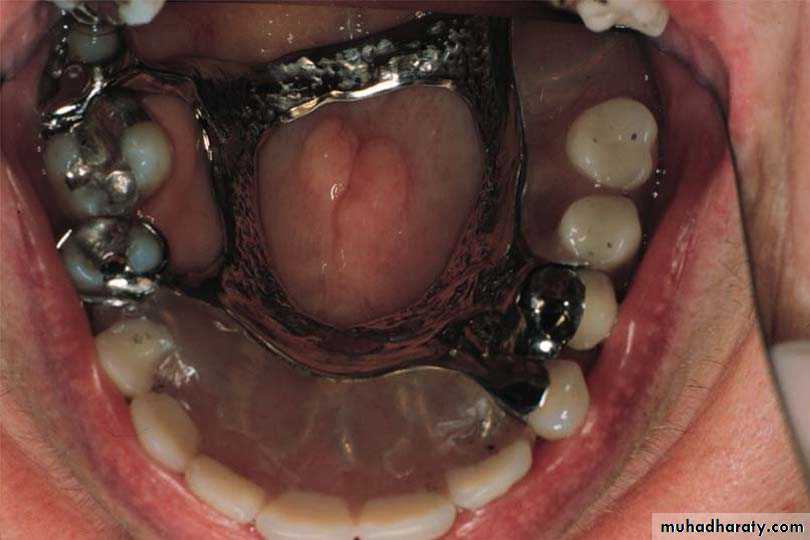

Type of Maxillary Major Connectors

3-U shape palatal connectors

3-Anterior Palatal Plate (cl I , II , IV)(U-Shaped or "Horse-Shoe" Palatal Connector)

Design:

1.It consists of U-shaped thin band of metal of 6-8mm in width.

2.The borders must be either 6mm away from the gingival margin or extend onto the lingual surfaces of the teeth.

3.The connector should be uniform in thickness, symmetric, and with curved and smooth borders

3

Note: the u shape palatal major connector is least favorable design of all palatal major connectors, because its lacks the rigidity of the other type